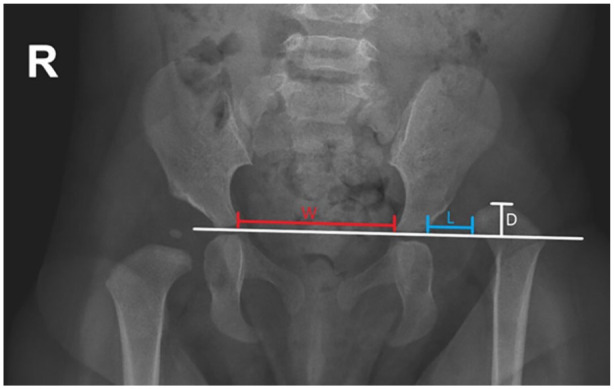

Methods: All open reduction surgeries for hip dislocations performed at a single urban, tertiary-care children's hospital from 2009 to 2023 were reviewed retrospectively. Those with connective tissue disorders secondary to a diagnosed syndrome or genetic disorder were included. Patients with <1 year of follow-up or hip instability in the setting of Trisomy 21 were excluded. Clinical and radiographic data was collected. Instances of re-dislocation, proximal femoral growth disturbance, residual acetabular dysplasia, and arthrofibrosis were recorded.

Results: Twenty-three hips (15 patients) were included. Mean age at the time of surgery was 19.6 months (Range: 8.2-36.0 months), and mean follow-up was 4.3 years. The most common connective tissue disorder condition included was Ehlers-Danlos syndrome (13%). A majority of open reductions were performed via an anterior approach (96%). Seven hips (30%) underwent a concomitant pelvic osteotomy without femoral osteotomy and seven hips (30%) underwent both pelvic and femoral osteotomies. Twenty-two hips (96%) were International Hip Dysplasia Institute grade 1 at the final follow-up. Re-dislocation occurred in four hips (17%); eight hips (35%) demonstrated residual acetabular dysplasia, five hips (22%) demonstrated proximal femoral growth disturbance, and nine hips (39%) developed stiffness postoperatively.